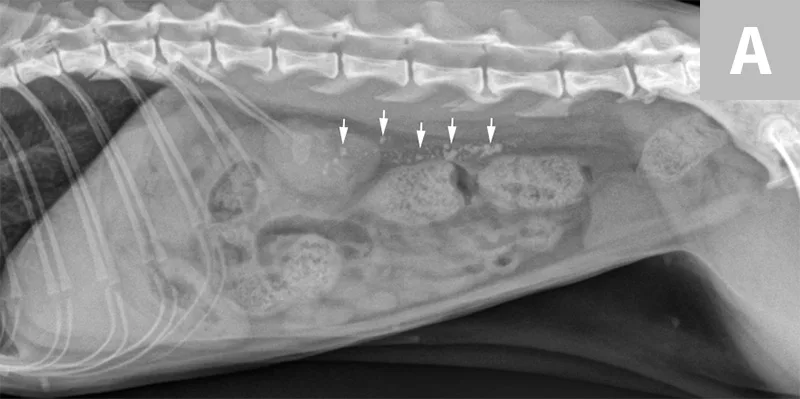

Lateral abdominal x-ray with five smooth radiopaque objects within bladder.

Lateral abdominal radiograph of a cat with multiple, small, oval mineral opacities superimposed over the ventral aspect of the retroperitoneal space (arrows). These mineral opacities are arranged linearly extending from the caudal aspect of the kidneys to the level of the urinary bladder.

Antegrade pyelography is beneficial when compared with standard IV urography, as it lowers the risk of potential contrast-induced renal damage and provides excellent filling of the renal collecting system, regardless of renal function.11